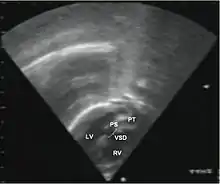

Abbreviations: LV and RV=left and right ventricle, PT=pulmonary trunk, VSD=ventricular septal defect, PS=pulmonary stenosis.